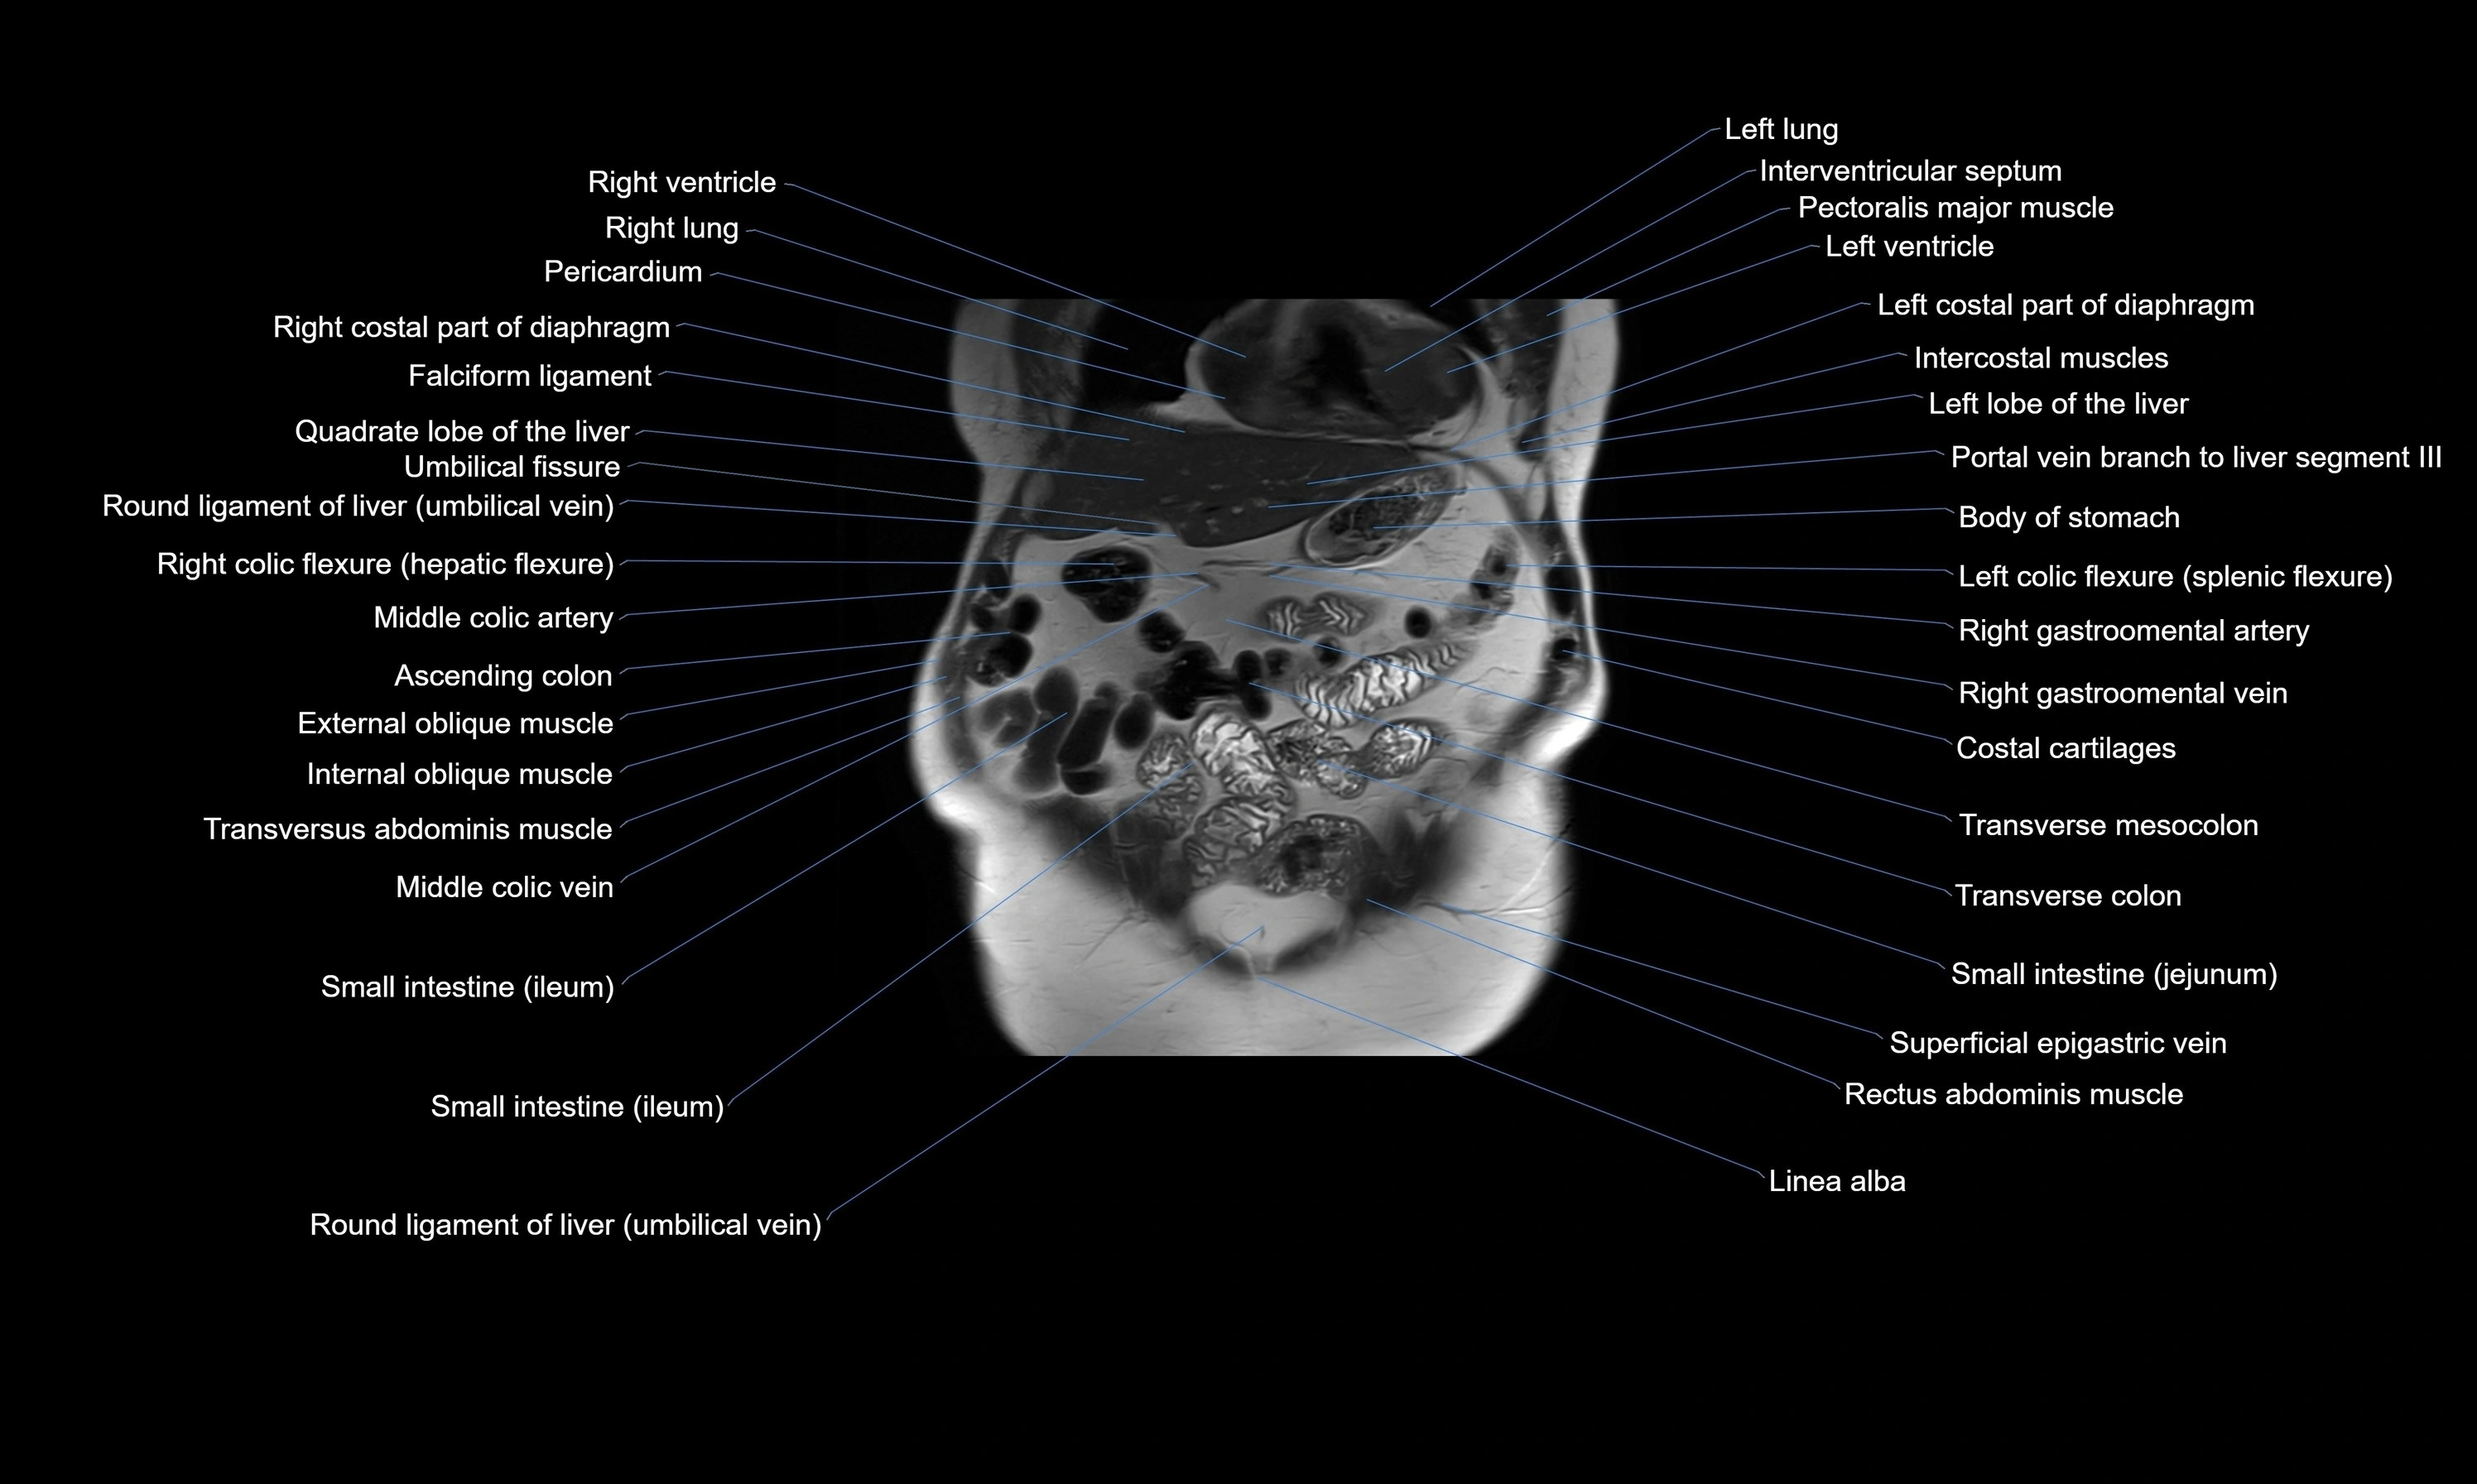

MRI images